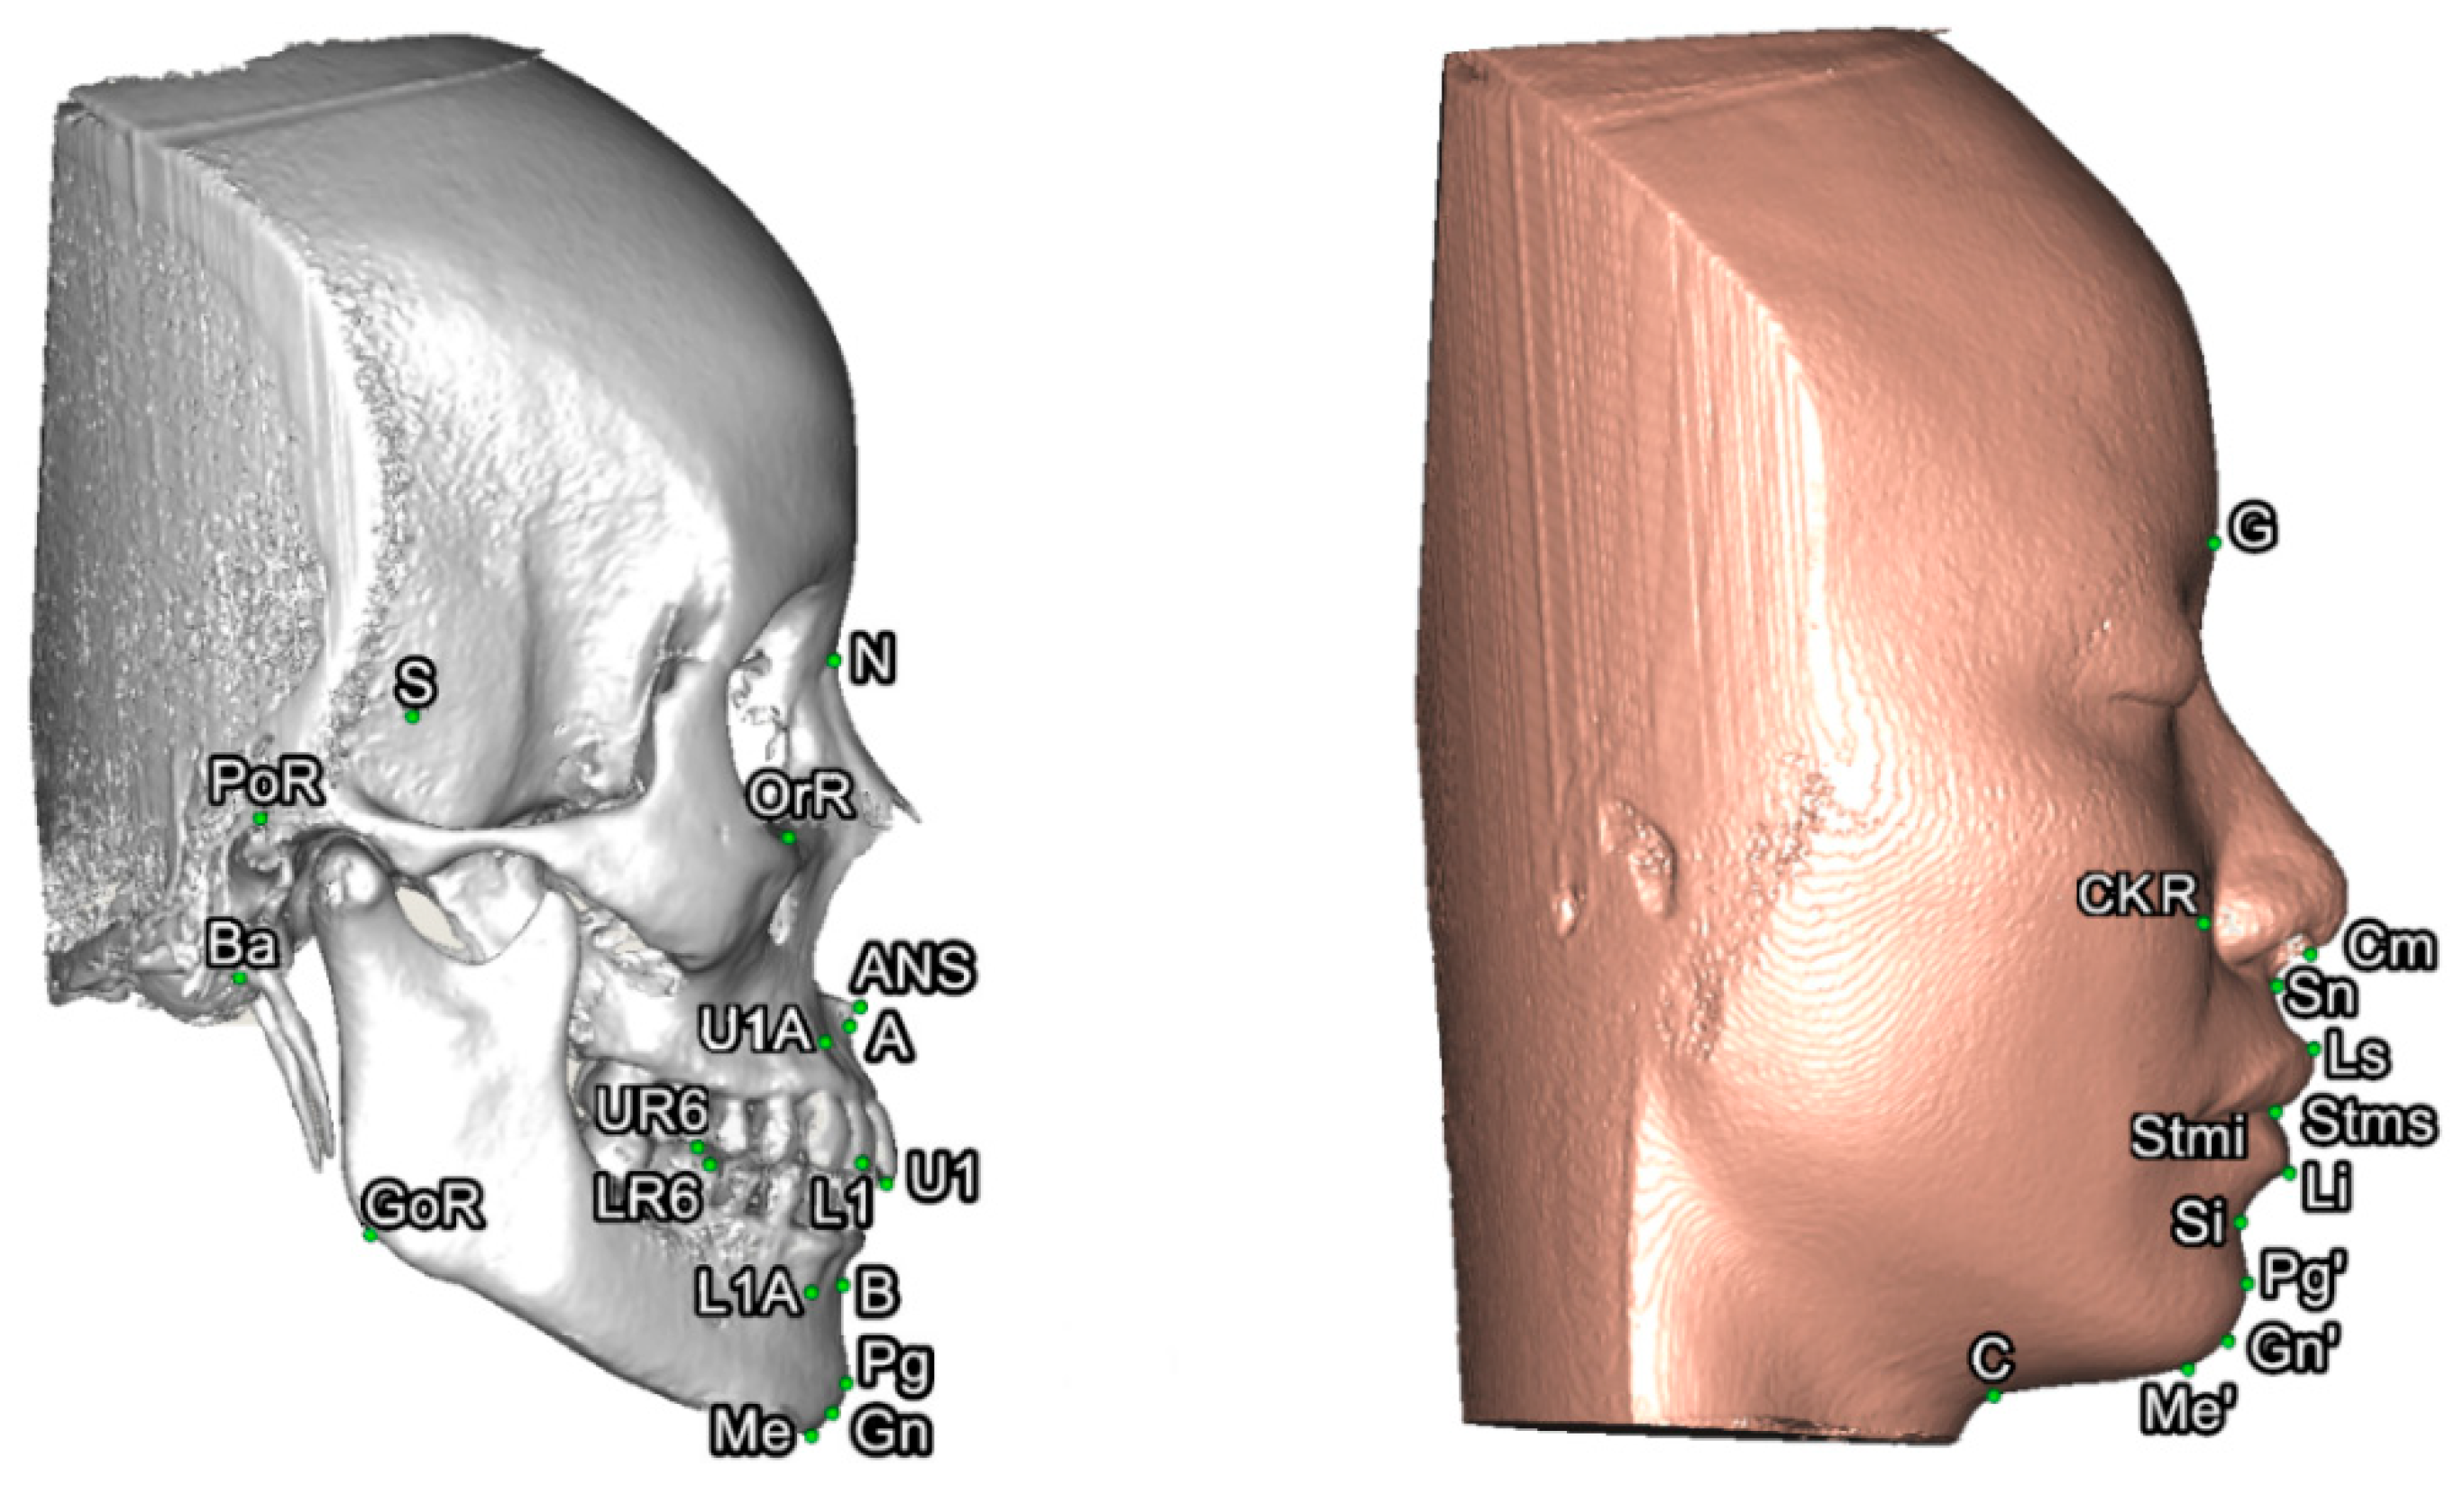

To set a normative database of 3D Burstone cephalometric measurements for Taiwanese Chinese, a total of 27 linear and nine angular measurements were generated using Simplant software. For this, all craniofacial bone and soft-tissue anatomical landmarks and reference planes (22, 14, and 8 parameters, respectively) were standardized based on previous descriptions (Table 1 and Table 2, Figure 2 and Figure 3) [11,12,33,34,35]. Two Burstone analysis-related anatomical landmarks (i.e., PtM and Ar) [11,12] were adapted; the anterior base length (S-N) replaced the cranial base length (Ar-PtM-N) and the Co-Go replaced Ar-Go for ramus length measurement. Due to the relevance of cheek prominence for overall aesthetic balance in Asians [25,36,37,38], a further parameter—that is, cheek mass (CK) (Figure 4)—was added to the Burstone soft-tissue analysis.

Figure 3. Three-dimensional skeletofacial model displaying the bone and soft-tissue landmarks adopted for cephalometric analysis. For definitions, please, refer to Table 1.